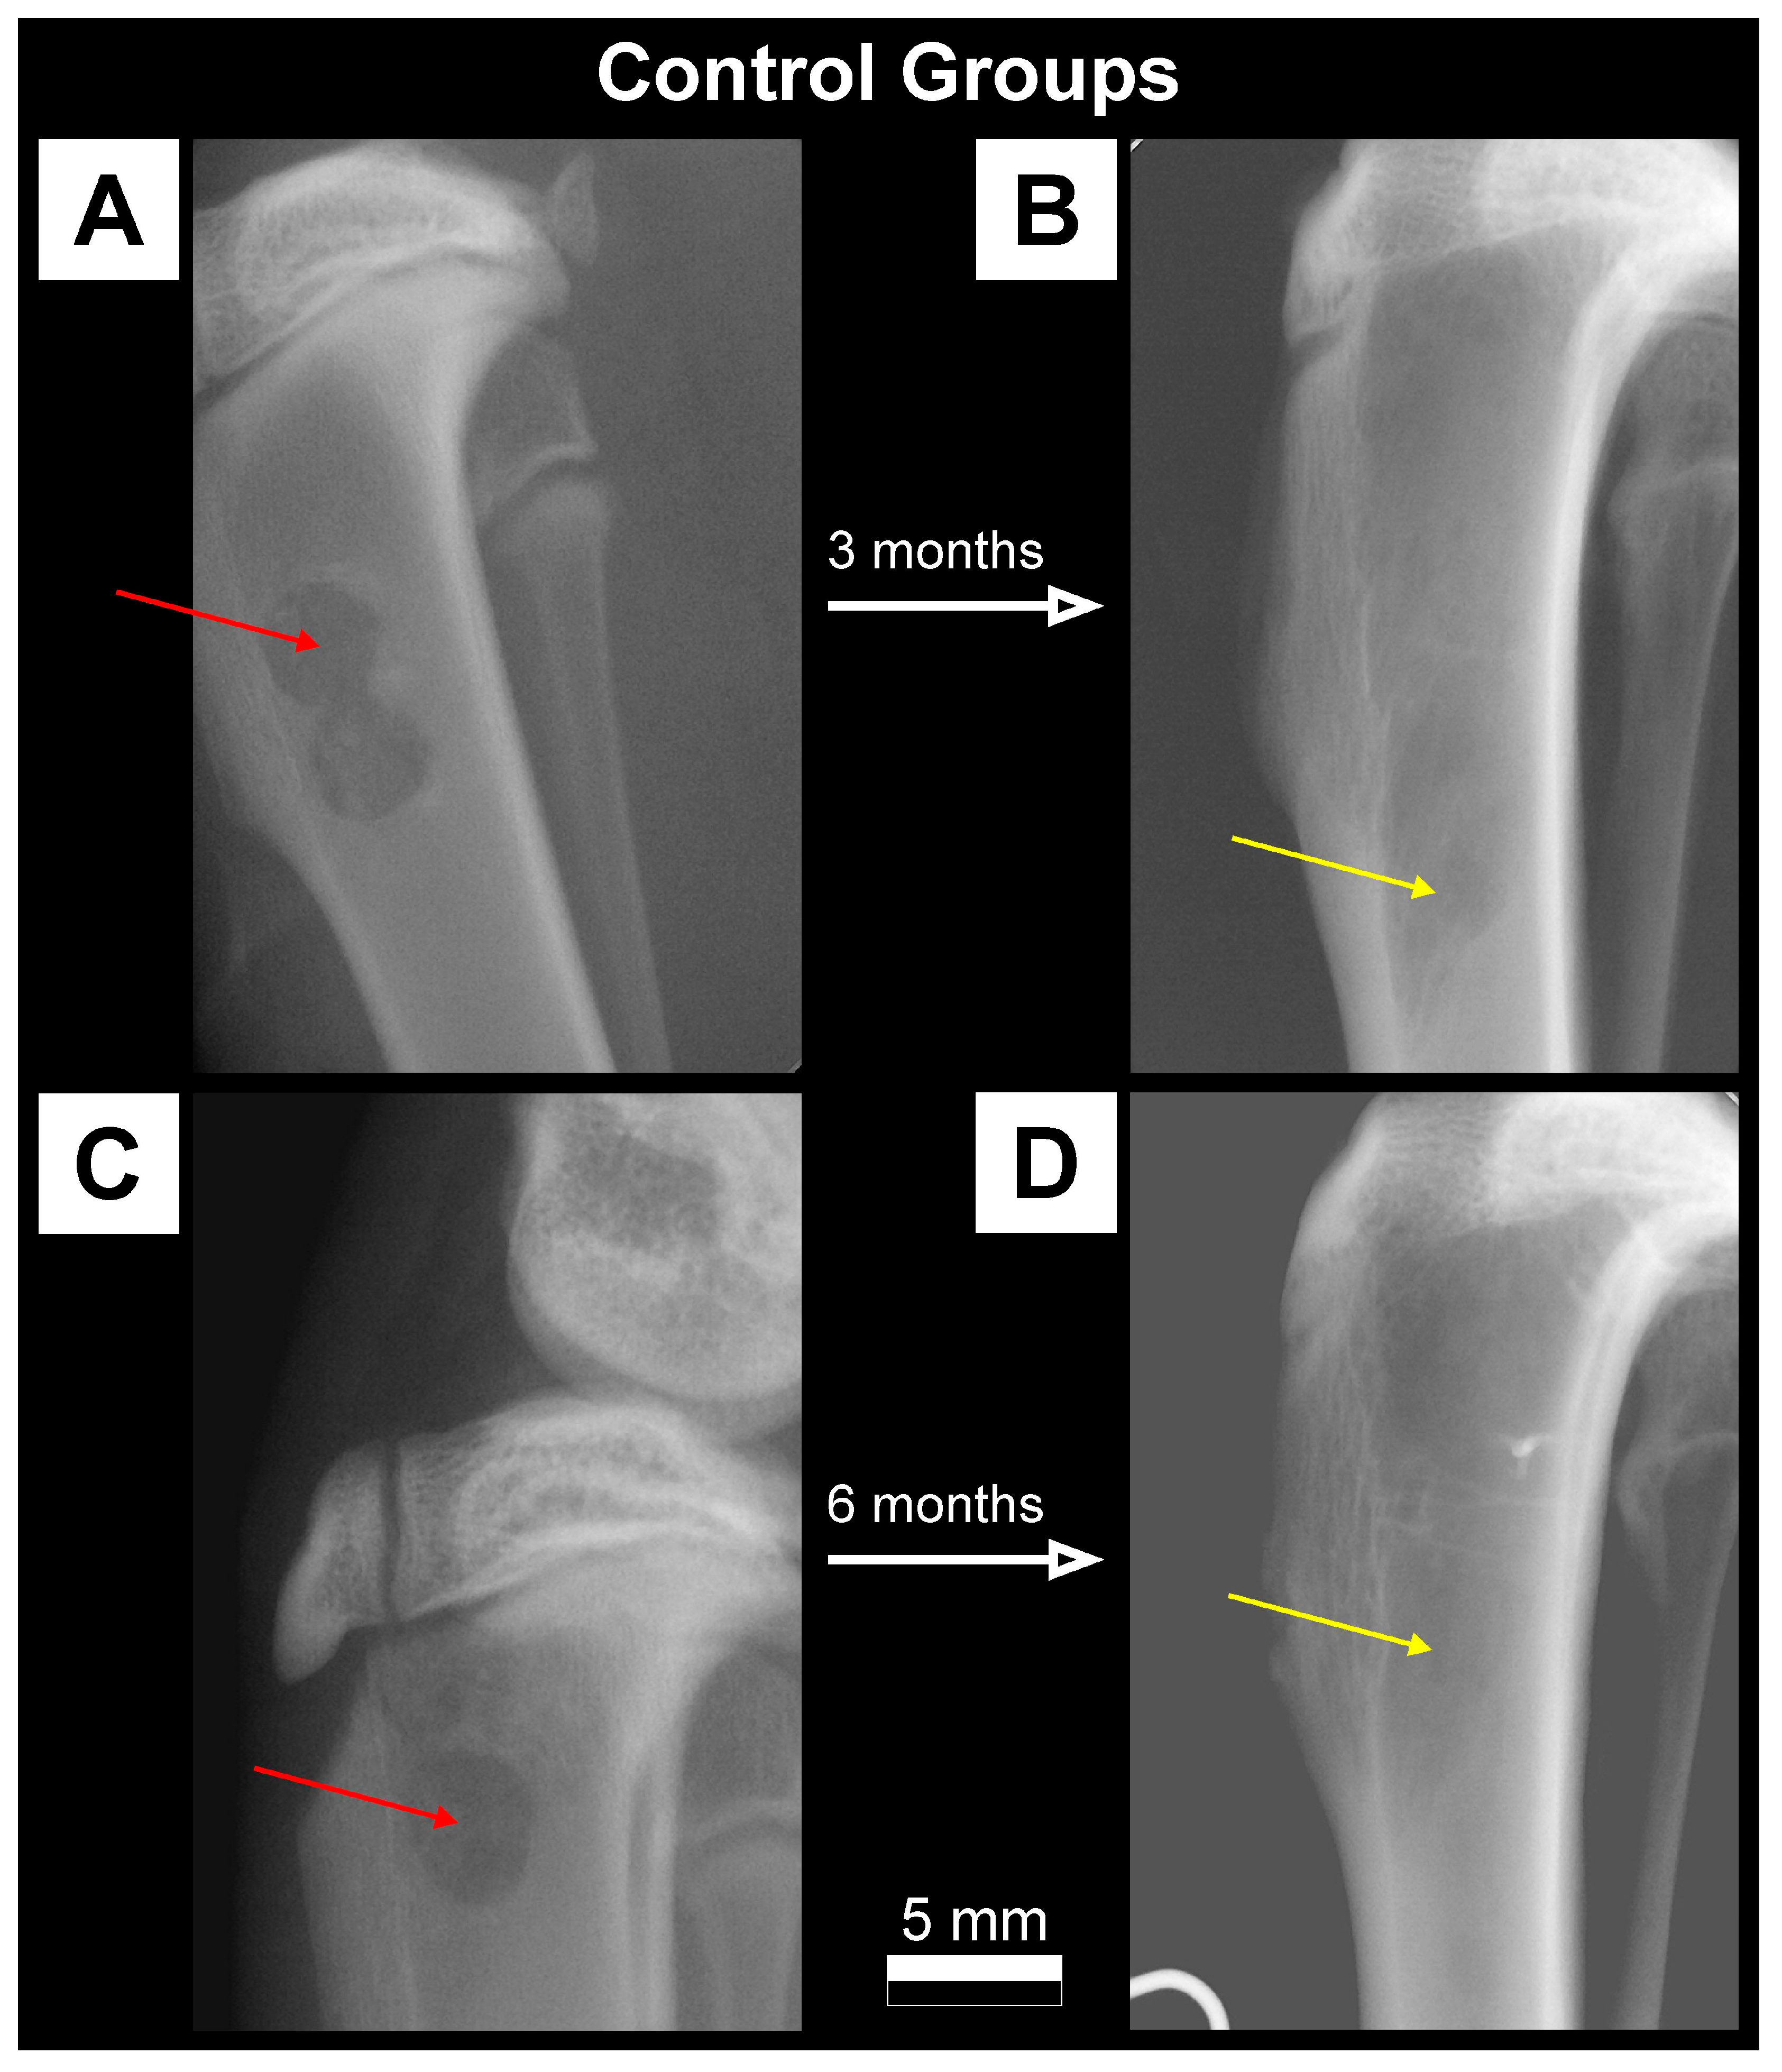

- Control: Rabbits that have undergone a “sham surgery”, with an empty hole in the bone left to heal (n = 10);

2.3.1. X-ray Imaging—Conventional Radiography

3.1. Qualitative Analysis of Bone Substitute Materials